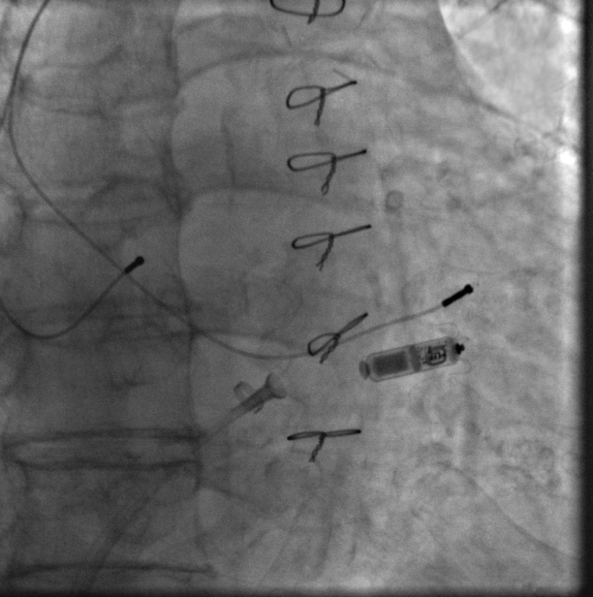

刘元伟、何榕医师在进行中

无导线起搏器及原导线